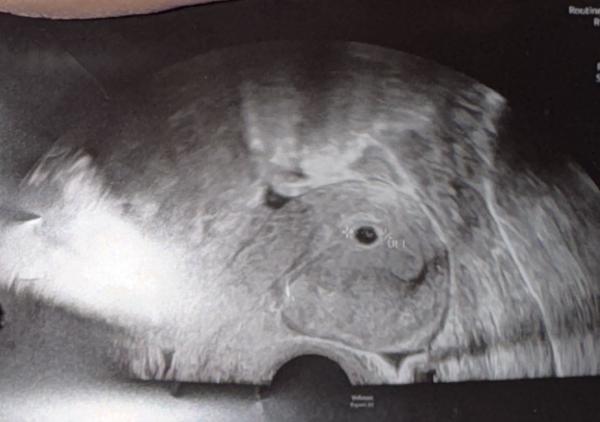

Hallo zusammen, ich hoffe ich bin hier richtig. ich hatte letzte Woche meinen ersten Ultraschall. Ich sehe zwei fruchthöhle auf dem ultraschallbild könnt ihr bitte mal schauen? vielen dank euch.

Hallo, es ist eine Fruchthöhle zu sehen. Und herzlichen Glückwunsch zur Schwangerschaft! Ich hab dir mal dein Bild nochmal eingefügt. Rot markiert ist der Umriss deiner Gebärmutter, darin sieht man die Fruchthöhle. Der schwarze Fleck außerhalb der Gebärmutter links oben ist ein Blutgefäß - die sehen auch so schwarz im Ultraschall aus.

Danke dir. Habe mir nur Sorgen gemacht weil ich oben auch etwas weises sehen kann.